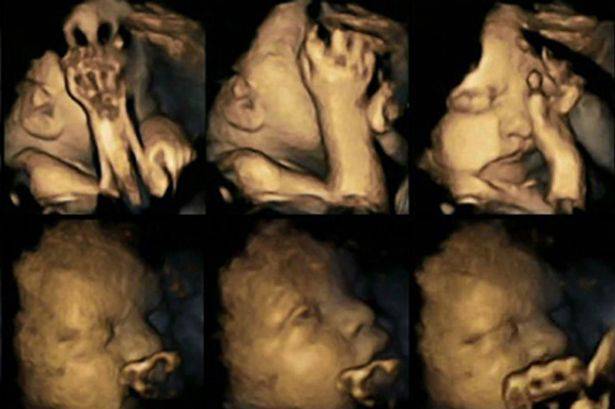

Una ricerca, condotta dalla Durham University e dalla Lancaster University, e pubblicata sulla rivista Acta Paediatrica, ha cercato di mostrare gli effetti del fumo sui bambini direttamente nel grembo materno, attraverso l’osservazione dei piccoli movimenti sui loro volti. Per produrre le immagini sono state utilizzate ecografie 4D.

La dottoressa Nadja Reissland, del Dipartimento di Psicologia della Durham University, ha studiato le immagini ed ha registrato migliaia di piccoli movimenti, monitorando 20 mamme presso l’University James Cook Hospital a Middlesbrough. Di queste 20 donne, 4 fumavano una media di 14 sigarette al giorno. Dopo aver studiato le scansioni a 24, 28, 32 e 36 settimane, la dottoressa ha rilevato che i feti le cui madri fumavano, mostravano tassi significativamente più alti di movimento della bocca e dei “toccamenti” rispetto ai tassi dei feti di madri non fumatrici. Questo perché di solito i feti verso la fine della gravidanza riescono ad ottenere un maggior controllo dei movimenti e riducono quindi il numero di volte in cui si toccano o muovono la bocca.